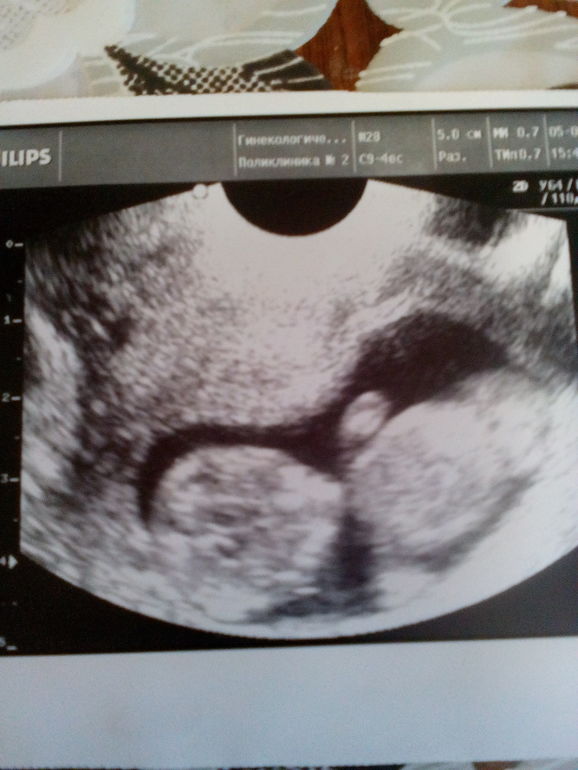

По узи- все в норме!!!

Ктр 67 мм,чсс- 160, кости носа определяются,твп 2,14( тут я что то напряглась- это нормально?) а вот и мы- ныряем под кат

Девочки, врач пол не сказала!! Как считаете,на кого похож))) срок ровно 13 нед,,,для сравнения фото сына на сроке 12 нед

Классный такой снимок. У меня ТВП была вроде 1,9, срок 11,6 по УЗИ был. Заметили мальчика.